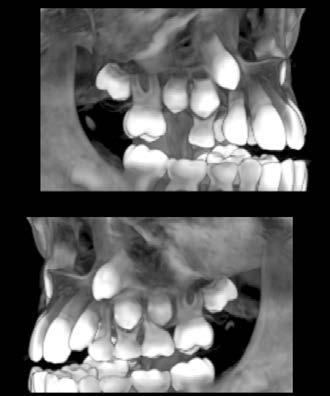

–Uso del anclaje esqueletal como alternativa eficiente en el manejo ortopédico de clases III por deficiencia de maxilar superior, por el Dr. Carlos Becerra y cols. [74]